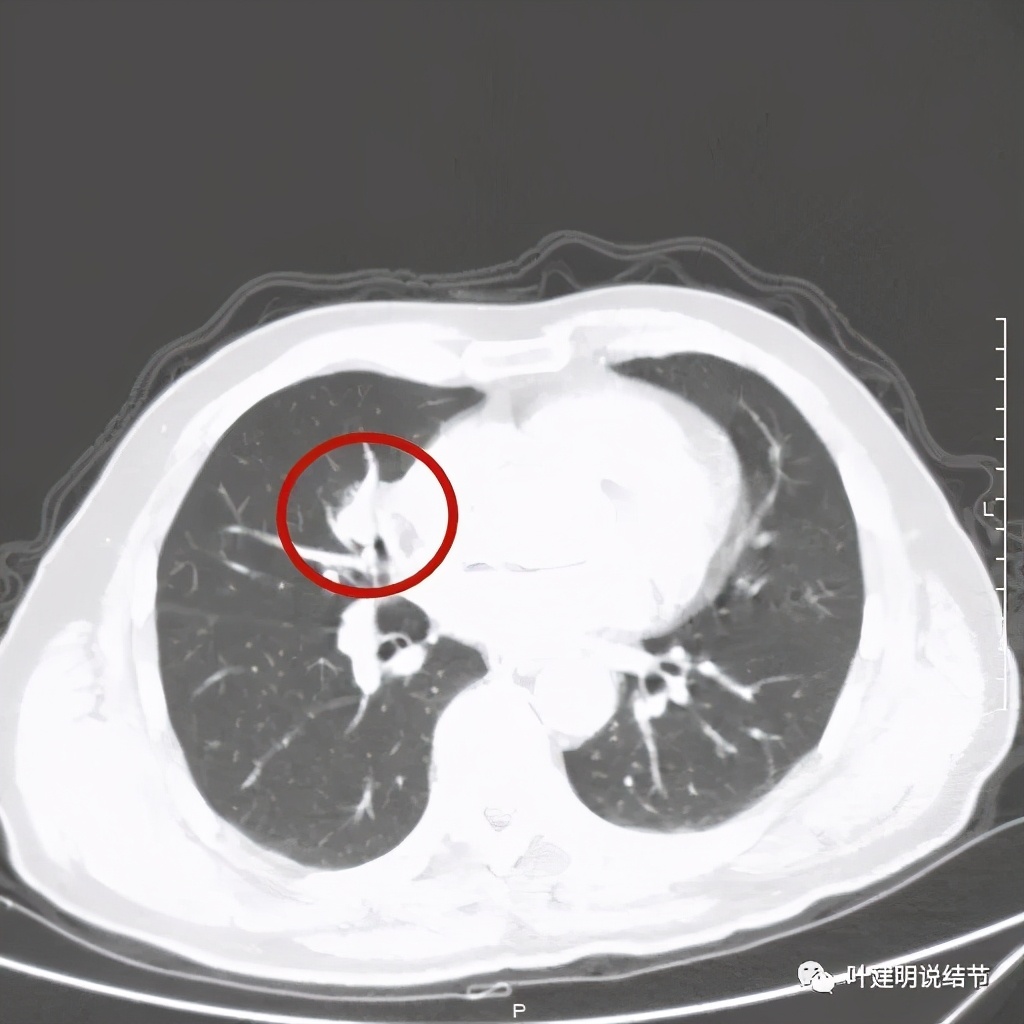

纵隔窗分叶明显,密度不均

黄色箭头示病灶附近淋巴结或癌结节可能性大

上图示血管被病灶影响,似乎有侵犯

上图示血管在病灶内挤压变细

上图示血管在病灶内被挤压

上图示支气管壁欠光整